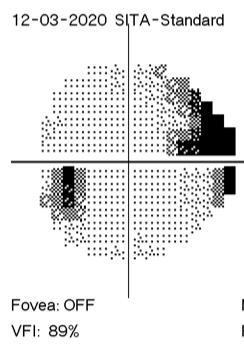

It is hard to explain how I see compared with how someone else sees when I don’t know differently. My visual is shown in the photographs below – this is my left eye (central 30 degrees) with darker areas representing field loss. The photo on the left is six months ago, and the photo on the right was around a week ago. I did not realise just how much had changed until putting these two photos side by side last week.